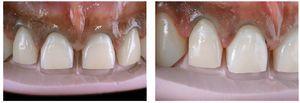

Figs. 9a a 9c. La situación 90 días después de la intervención quirúrgica y un blanqueamiento de dos semanas en casa. El recorrido gingival sigue la línea labial inferior y ya no se aprecia sonrisa gingival

Figs. 10a y 10b. El nuevo recorrido gingival.